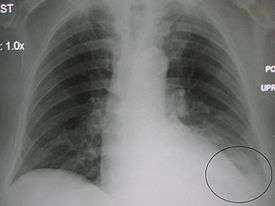

Parapneumonic effusion

Diagnostic techniques available include plain film chest x-ray, computed tomography (CT), and ultrasound. Ultrasound can be useful in differentiating between empyema and other transudative and exudative effusions due in part to relative echogenicity of different organs such as the liver (often isoechogenic with empyema).